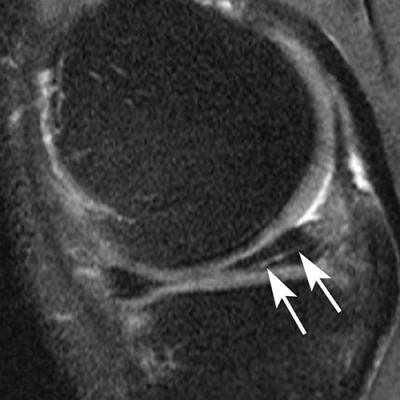

Sagittal intermediate-weighted fat-saturated image shows a typical horizontal-oblique meniscal tear of the posterior horn reaching the undersurface of the meniscus (arrows).